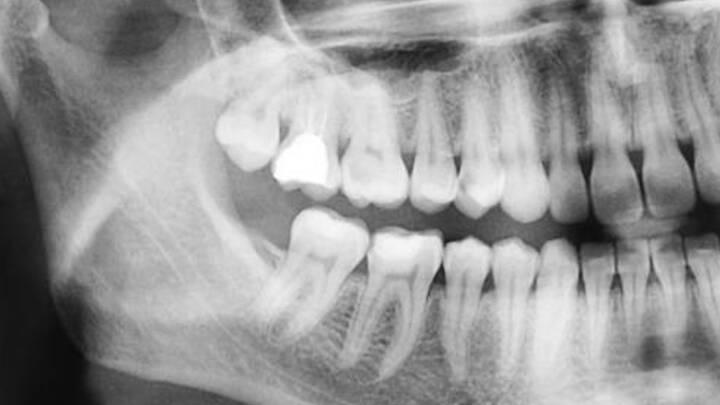

В Саратове свадебное торжество завершилось потасовкой. 26-летний мужчина на Набережной Космонавтов поссорился с 20-летним гостем и ударил его в челюсть. Пострадавшего госпитализировали. Врачи диагностировали у парня открытый перелом нижней челюсти.